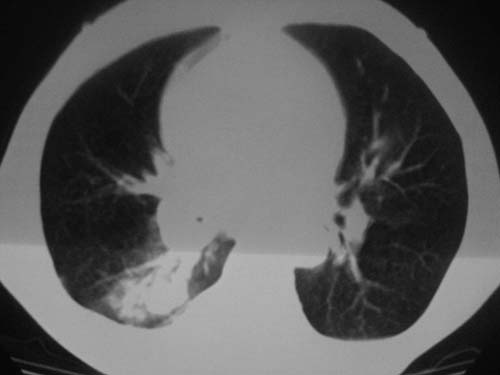

以下是引用科室第一人在2010-3-25 20:30:00的发言:[br]1:纵膈肿瘤性病变,恶性胸腺瘤可能性大伴纵膈右肺门淋巴结转移,右侧胸腔积液。[br]2:右侧肺门肿瘤性病变,纵膈淋巴结转移,右侧胸腔积液。右下叶转移。

以下是引用子期在2010-3-25 21:00:00的发言:[br]先考虑右中央型肺癌伴转移。

以下是引用江广1996在2010-3-25 22:49:00的发言:[br]通常肺癌向纵隔转移多见,纵隔肿瘤向肺内转移少见(有的表现为向肺内侵润)。本例以一元论考虑:右中心型肺癌并纵隔淋巴等多处转移。[br][br][本贴已被 江广1996 于 2010-3-25 22:50:07 修改过]

以下是引用yangyudong333在2010-3-26 6:43:00的发言:[br]“冰冻纵膈”,考虑纵膈淋巴瘤伴肺内及胸膜侵润。